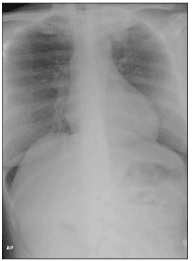

Laboratory analysis revealed a white blood cell count of 3400/µL, with 80% neutrophils and 12% lymphocytes; a hematocrit of 28% with normal platelet count; albumin, 2.9 g/dL; and serum protein, 7.7 g/dL. A chest radiograph revealed a left upper lobe infiltrate (Figure 1). A chest CT scan further characterized this apical infiltrate as a mass-like consolidation with associated lymphadenopathy (Figure 2).

Figure 1.Chest radiograph showing a left apical mass-like opacity. (Illustration courtesy of the department of radiology, New York Presbyterian Hospital–Weill Medical College, Cornell University, New York.)